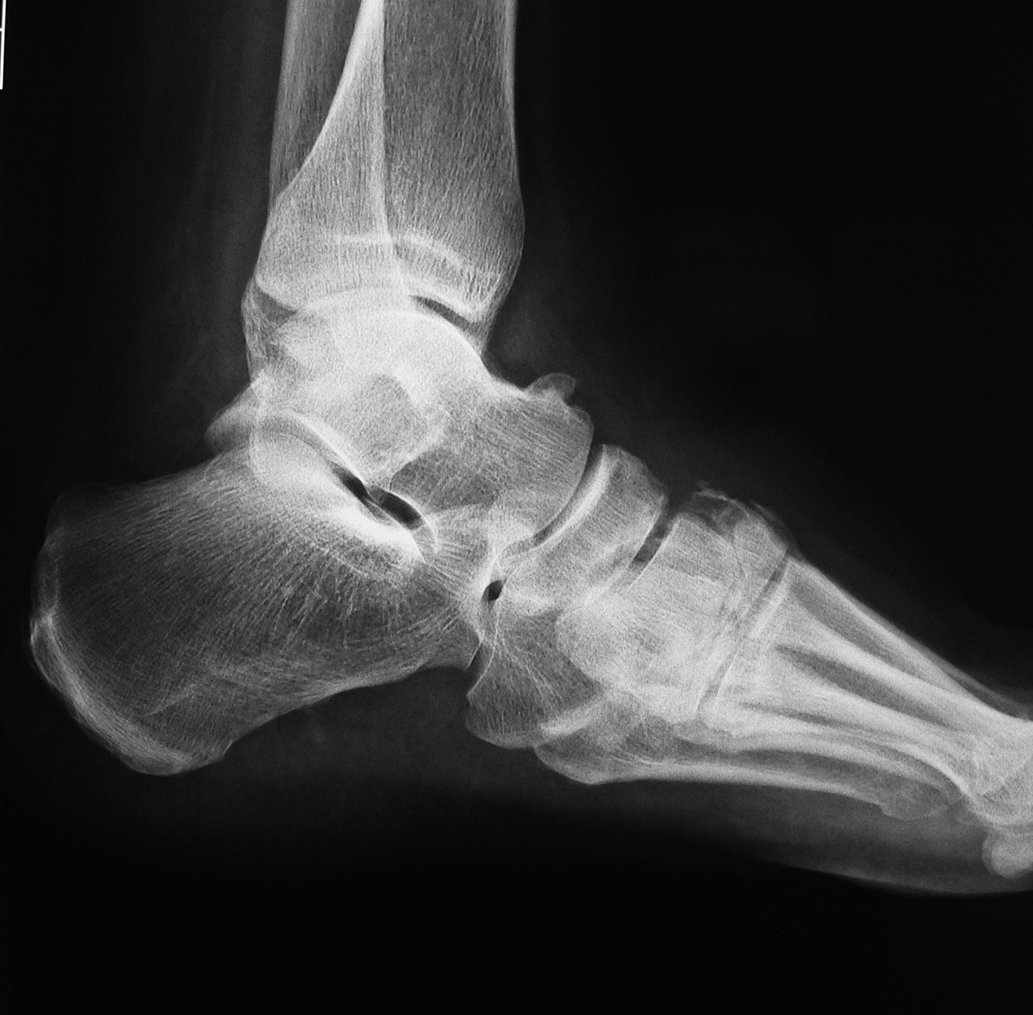

На рентгенограмме (начало октября 2018 г.) отмечается небольшая дислокация ладьевидной кости, нечеткость границ II, III клиновидных костей (возможное их разрушение), а также неизвестной давности экзостоз таранной кости (рис. 5, 6). В связи с неоднозначностью рентгенологических данных выполнена МР-томография. Выявлен отек костного мозга таранной, ладьевидной, кубовидной кости, деструкция клиновидных костей.

Рис. 5. Рентгенограмма стопы больного 2. Прямая проекция.

Рис. 6. Рентгенограмма стопы пациента 2. Боковая проекция.

Таким образом, установлен диагноз: Диабетическая нейроостеоартропатия левой стопы, активная стадия 1 (рентгенопозитивная) с поражением среднего и заднего отделов стопы; диабетическая макроангиопатия нижних конечностей, ишемия 1 (по классификации Лериша–Фонтена–Покровского) после чрескожной транслюминальной баллонной ангиопластики.

Сравнение рентгенологической картины и результатов МРТ продемонстрировало преимущество последнего. Так, в обоих случаях зона поражения по МРТ была больше, чем видимая на рентгенограмме. Кроме того, как показано на рис. 7, данные МРТ можно использовать для мониторирования эффективности лечения. Эти факты подтверждают преимущества применения МРТ в ведении пациентов с активной ДНОАП [8].